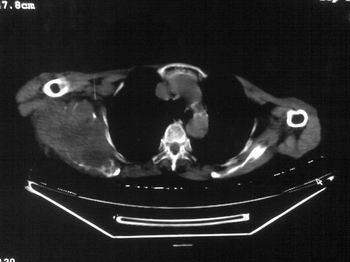

以下是引用dyqct在2007-9-11 16:52:00的发言:[br]支持右肩胛骨恶性肿瘤,性质不好定。

以下是引用zhangxu5888在2007-9-11 16:25:00的发言:[br]有侧肩胛骨溶骨性破坏且见软组织成分,增强软组织强化明显,中央见低密度坏死区!根据病史10年,考虑良性肿瘤恶性变!性质待定!

以下是引用老爱克斯新网客在2007-9-11 18:22:00的发言:[br]应该是良性肿瘤恶变,但因晚期破坏严重不能见到原来肿瘤征象无法判断,